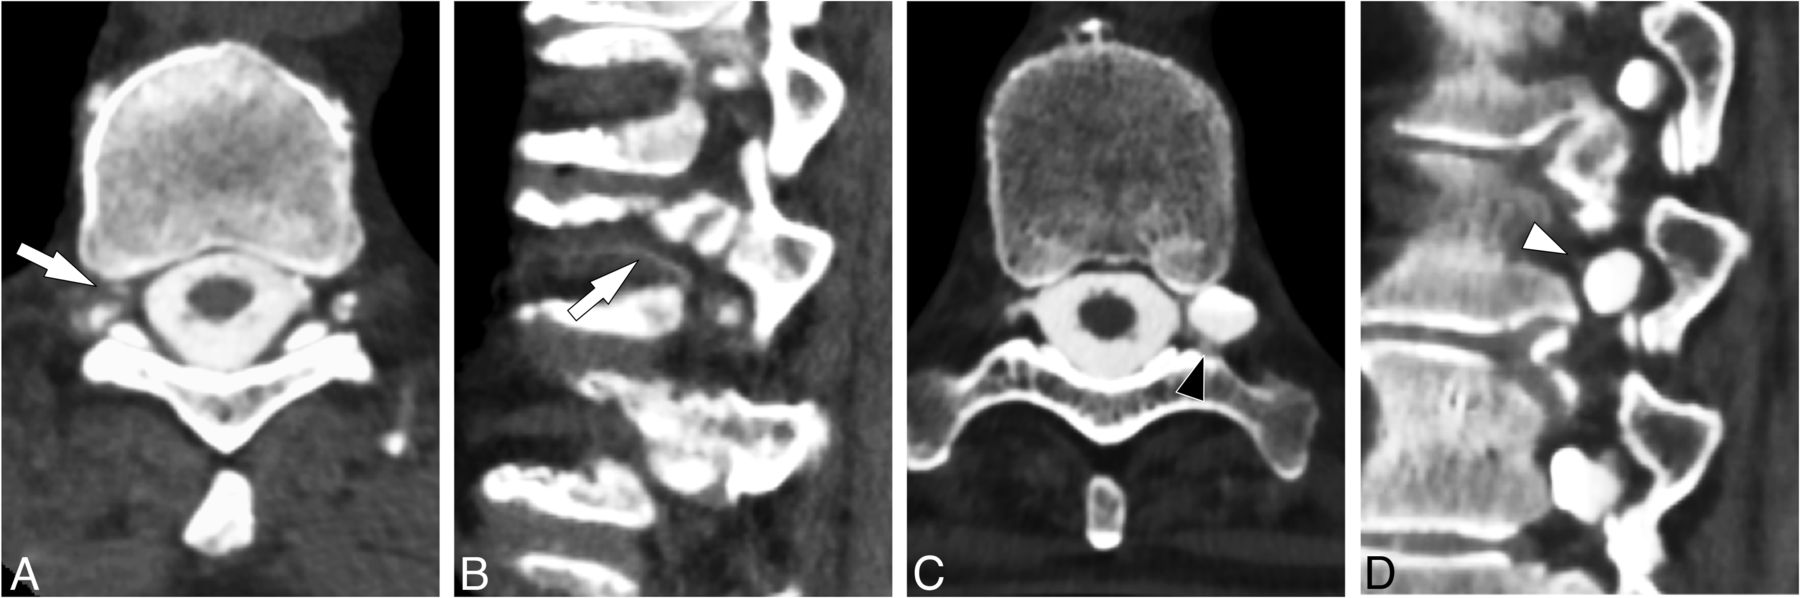

CT myelograms were reviewed to determine the presence of a CVF. Assessment was based on the presence of a “hyperdense paraspinal vein” sign and was performed by 1 of 2 study neuroradiologists with 12–15 years’ experience evaluating CTM for SIH (Fig 2).11 In equivocal cases, the imaging was jointly reviewed by both neuroradiologists to reach a consensus (Fig 3).

Examples of equivocal CVFs requiring adjudication. Axial (A) and sagittal (B) images from CTM in a single subject show subtle increased attenuation of a foraminal vein and adjacent segmental spinal vein (white arrows); this increased attenuation was judged to represent a CVF after a consensus read. Axial (C) and sagittal (D) images from CTM in a second subject whose faint increased attenuation posterior to the perineural diverticulum (black arrowhead) and anterior to the same diverticulum (white arrowhead) was judged to be not definitive enough to diagnose as a CVF following consensus read.